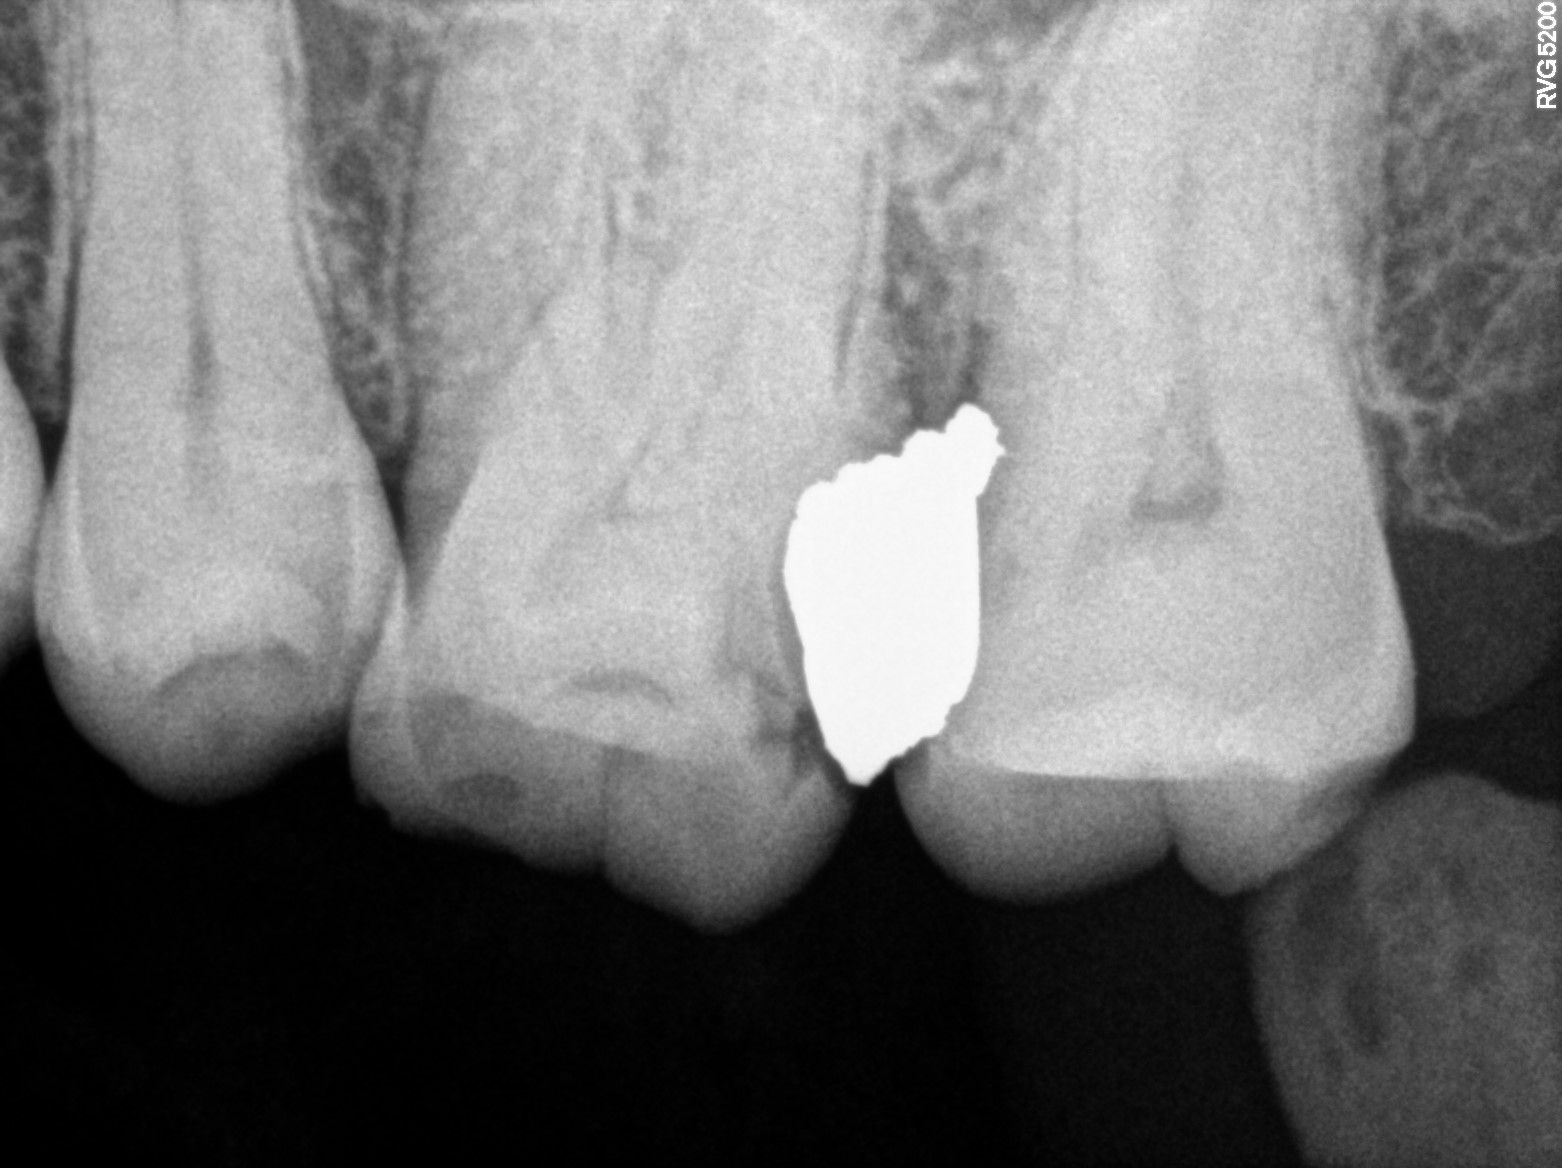

Dental Radiographs FHIR: DocumentReference · LOINC 24641-7

xray_1741706089.jpg

24641-7